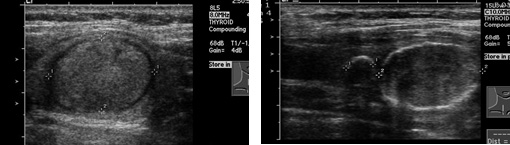

갑상선종양의 진단도가 가장 정확한 방법입니다. 갑상선 초음파 검사로 결절의 크기, 모양, 위치, 결절의 갯수 등을 알 수 있을 뿐 아니라 결절의 낭성 변화(혹 속에 피나 물이 고이는 경우)나 낭종(물혹)을 확인할 수 있습니다. 경계가 좋지 않은 결절, 내부에코가 불균등 한 경우 및 갑상선 밖으로 침범하는 모양을 보이는 멍울주위에 임파절이 커져있는 경우 갑상선 암을 의심할 수 있습니다.